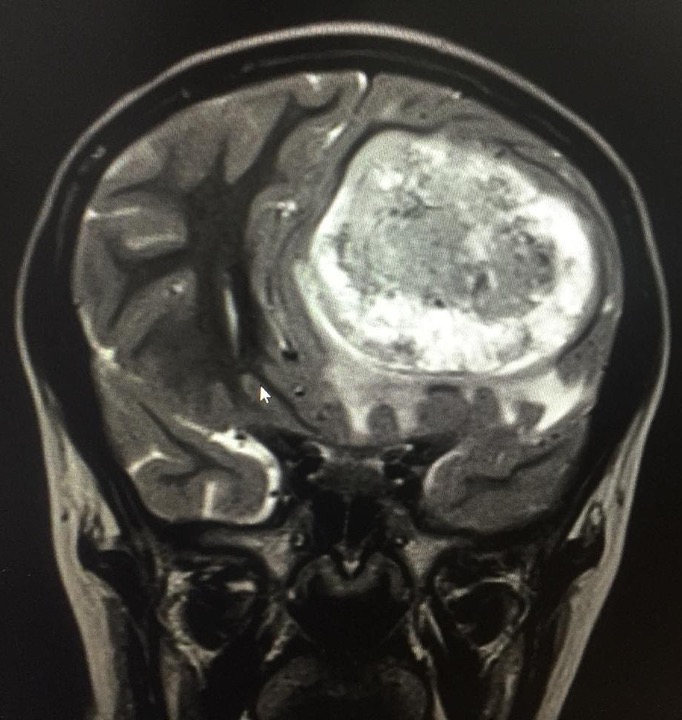

Al examen neurológico se evidencia que la paciente presenta dolor de 6/10 por escala análoga del dolor y papiledema derecho, sin focalización, resto del examen físico normal. Por lo anterior se consideró paciente con cefalea con banderas rojas por lo que se solicitó resonancia magnética cerebral simple. Se evidenció lesión expansiva intra-axial de aspecto heterogéneo en todas las secuencias con predominio de hipointensidad en T1 e hiperintensidad en T2 que se rodea de escaso edema perilesional con escaso componente hemorrágico hacia posterior con restricción de la difusión, con diámetros de 66.44mm anteroposterior x 52.11 mm de alto x 58 mm de ancho.

Adicionalmente, presentaba importante efecto compresivo que desvía a las estructuras de la línea media de izquierda a derecha por debajo de la hoz y deforma el sistema ventricular, con hernia del hipocampo izquierdo (Ver figura 1). Ante estos hallazgos el servicio de neurología solicitó una resonancia magnética contrastada e inició tratamiento con analgesia y corticoides para prevención de hipertensión endocraneana. Ante los hallazgos descritos, se realizó una junta con los servicios de neuroradiología, neurocirugía y hematooncología pediátrica quienes consideraron que se trataba de tumor glial (oligodendroglioma) en lóbulo frontal izquierdo que se asociaba a herniación cerebral subfalcina con desviación de línea media de 1.6mm, con edema cerebral vasogénico e importante efecto de masa que se acompañaba de síntomas de hipertensión endocraneana (cefalea, emesis y papiledema).

Figura 1. Resonancia magnética cerebral

A. Corte Axial B. Corte coronal. Lesión expansiva intra-axial de aspecto heterogéneo con predominio de hipointensidad en T1 e hiperintensidad en T2 que se rodea de escaso edema perilesional con escaso componente hemorrágico hacia posterior con restricción de la difusión. Diámetros de 66.44mm AP x 52.11 mm de alto x 58 mm de ancho. Importante efecto compresivo que desvía las estructuras de la línea media de izquierda a derecha por debajo de la hoz y deforma el sistema ventricular, con hernia del hipocampo izquierdo